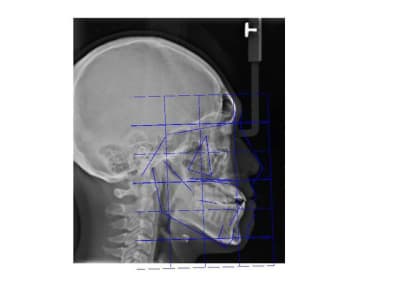

Ci joints photos, ceph, modeles.

Une question, les analyses et la prevision faite sur la radio, sont faite pour un type caucasian ou asiatique????

Ils ont utilisé une analyse adapté au patient.

Ensuite ça dépend des populations tu a les normes pour coréen, japonais, Thai du nord et Thai du centre , chinois ect ect. A priori la population la mieux suivit en Asie c'est les japonais ils rétablissent leur nomes tout les dix ans.

On a des mesh et des normes pour :

-Caucasiens

-Afro américains

_Asiatiques

-Latinos

Le mesh utilisé ici est un asian mesh.

Par ailleurs ce n'est pas une prévision finale du traitement, c'est une aide au dignostic à base de normes préétablies de positionnement des points de repères.